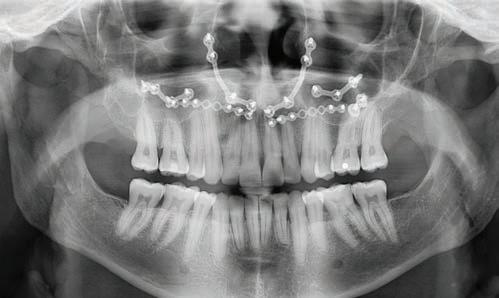

The panoramic radiograph (Figure 3) highlights the three missing premolars and absence of all third molars. Root length is excellent and periodontal support is good. The patient’s restorative index is low, a reflection of his history of regular dental care and good oral hygiene. The cephalometric radiograph, and analysis (Figure 4a and 4b) suggest a near-Class I skeletal relationship with mildly increased skeletal vertical dimension (MPA 35.8). Mandibular incisor angulation is significantly below average (IMPA 84.7), relative to the steeper than average mandibular plane. Visually, incisor angulation appears to be normal.

Figure 3: INITIAL panoramic radiograph Figures 4a and 4b: Initial cephalometric radiograph and analysis